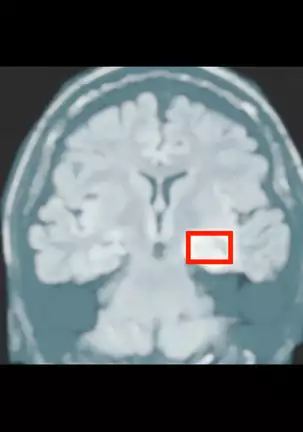

(C85) [Punipuni Doumei (Mizuki Gyokuran)] Noukou Mate (Ore no Nounai Sentakushi ga, Gakuen Love Comedy wo Zenryoku de Jama Shiteiru)